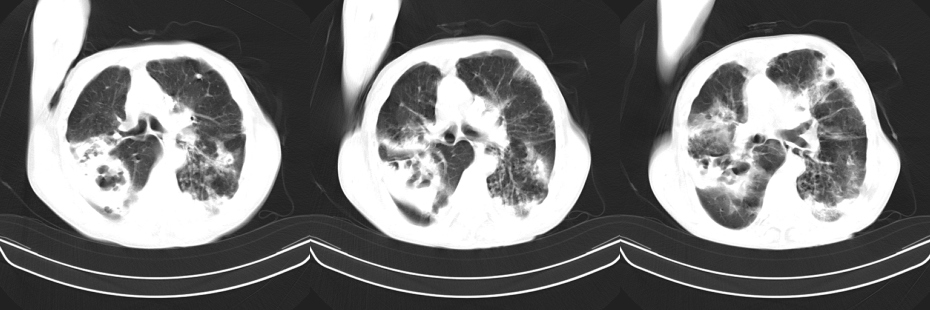

以下是引用mzh123在2007-8-26 19:58:00的发言:[br]两肺弥漫性斑片改变,其中可见大小不等之不规则空洞,结合既往病史还是考虑结核复发及感染。

以下是引用云翔在2007-8-26 20:54:00的发言:[br]这是44岁的肺吗?是否有先天病的基础?干酪性肺炎?